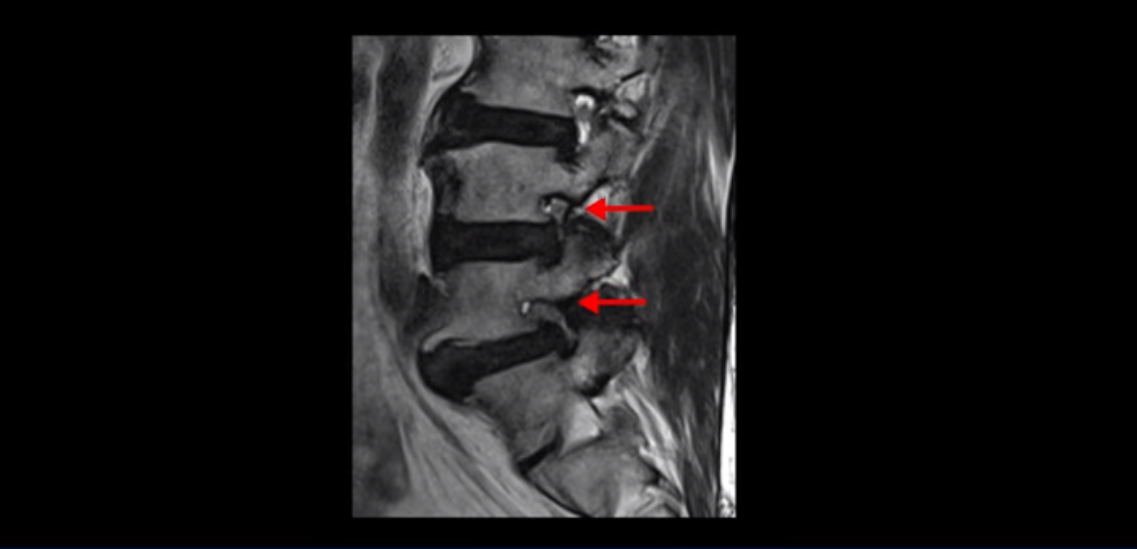

이분은 허리 다섯 마디 중 4번 5번, 5번 1번에 감압술로 눌린 신경을 풀어주는 수술을 받았습니다.

후관절을 떼어낸 흔적이 보입니다.

단면으로 보면 왼쪽 후궁을 제거한 흔적이 보입니다.

5번 1번도 왼쪽 후궁을 열고 수술 받았습니다.

하지만 중심성 협착은 여전히 심한 상태입니다.

이분은 오른쪽, 왼쪽 다리에 모두 방사통이 심하고 왼쪽 다리에 마비 증상, 즉 풋드랍(족하수) 증상이 있습니다. 왼쪽 신경 가지가 빠져나가는 추간공을 보면 두 마디가 좁아져 있습니다.

이미 앞선 두 번의 수술로 뼈와 인대 등을 일부 제거해서 안정성이 떨어진 상태에서 추가로 수술하려니까 척추가 너무 불안정해져 무너질 게 걱정되니까 이번에는 나사 박는 유합술을 권유 받은 겁니다. 이런 환자분들의 방사통과 마비 증상이 어떻게 수술 없이 좋아질 수 있을까요? 치료는 어떻게 하는 걸까요?